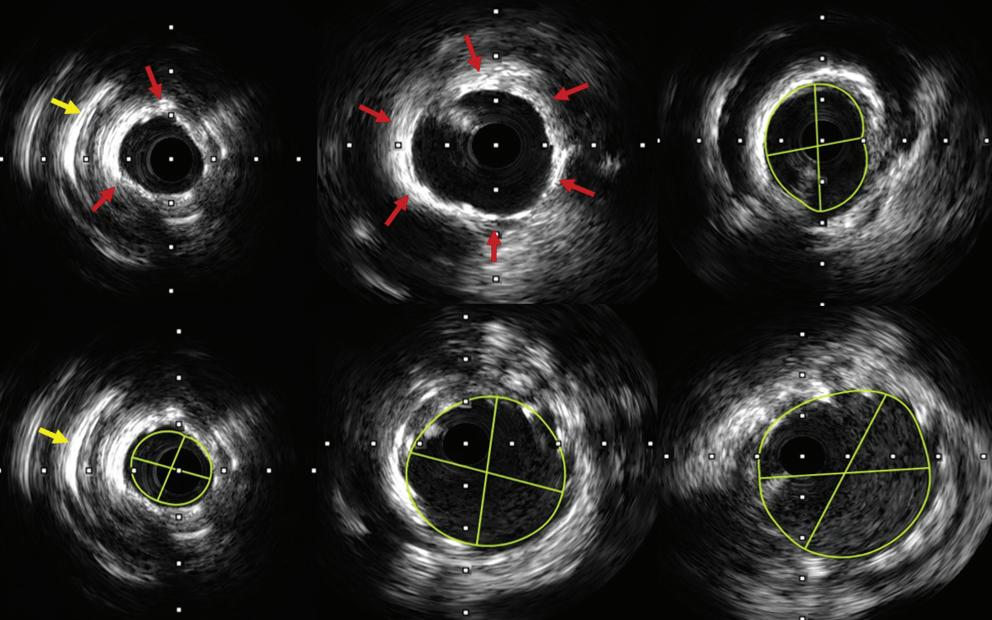

7. Smedema JP, Van Kroonenburgh MJ, Snoep G, et al. Cardiac sarcoidosis in a patient with hypertrophic cardiomyopathy demonstrated by magnetic resonance imaging and single photon emission computed tomography dual-isotope scintigraphy. Circulation 2004;110:e529–31.

https://doi.org/10.1161/01.CIR.0000149749.95902.A4; PMID: 15596554.

Cardiac Sarcoidosis, Pericardial Effusion and Stress-induced Cardiomyopathy JOURNAL OF ASIAN PACIFIC SOCIETY OF CARDIOLOGY www.JAPSCjournal.com

European Examination in Core Cardiology (APSC Exit Examination)

Jack WC Tan,1,2,3 Jonathan Yap,1,2 Khung Keong Yeo,1,2 Derek P Chew,4 Alan Yean Yip Fong,5,6 Caitlyn Tan,7 Abdul Shehab,8 Nguyen Ngoc Quang,9 Terrence Chua,1 Clive Lawson,10 Danny Mathysen,11,12 Stephanie Thibault,13 Wael Al Mahmeed14 and Chris Plummer15

1. Department of Cardiology, National Heart Centre Singapore; 2. Duke-NUS Medical School, Singapore; 3. Department of Cardiology, Sengkang General Hospital, Singapore; 4. Department of Cardiology, Flinders University College of Medicine and Public Health, Adelaide, Australia; 5. Department of Cardiology, Sarawak Heart Centre, Kota Samarahan, Sarawak, Malaysia; 6. Faculty of Medicine and Health Sciences, University Malaysia Sarawak, Kota Samarahan, Sarawak, Malaysia; 7. National University of Singapore Yong Loo Lin School of Medicine, Singapore; 8. College of Medicine and Health Sciences, UAE University, Al Ain, United Arab Emirates; 9. Department of Cardiology, Hanoi Medical University, Hanoi, Vietnam; 10. Department of Cardiology, Maidstone and Tunbridge Wells NHS Trust, Maidstone, UK; 11. Department of Ophthalmology, Antwerp University Hospital, Edegem, Belgium; 12. Faculty of Medicine and Health Sciences, University of Antwerp, Wilrijk (Antwerp), Belgium; 13. European Society of Cardiology (ESC), Biot, France; 14. Heart and Vascular Institute, Cleveland Clinic, Abu Dhabi, United Arab Emirates; 15. Department of Cardiology, Freeman Hospital, The Newcastle upon Tyne Hospitals NHS Foundation Trust, Newcastle upon Tyne, UK

Keywords

European Examination in Core Cardiology (EECC), Asian Pacific Society of Cardiology (APSC), Asia–Pacific, exit examination, core cardiology

Disclosure: JWCT is on the Editorial Board of the Journal of Asian Pacific Society of Cardiology; this did not influence peer review. JWCT has received honoraria from AstraZeneca, Bayer, Amgen, Medtronic, Abbott Vascular, Biosensors, Alvimedica, Boehringer Ingelheim and Pfizer; research and educational grants from Medtronic, Biosensors, Biotronik, Philips, Amgen, AstraZeneca, Roche, Otsuka, Terumo and Abbott Vascular; and consulting fees from Elixir, CSL Behring and Radcliffe Publishing. JY is an Associate Editor of the Journal of Asian Pacific Society of Cardiology; this did not influence peer review. KKY is Editor-in-Chief of the Journal of Asian Pacific Society of Cardiology; this did not influence peer review. KKY has received institutional research funding from Medtronic, Boston Scientific, Amgen, AstraZeneca and Shockwave Medical; consulting or honoraria fees from Medtronic, Boston Scientific, Abbott Vascular, Amgen, Bayer and Novartis; and speaker or proctor fees from Abbott Vascular, Boston Scientific, Medtronic, Philips, Shockwave Medical, Alvimedica, Menarini, AstraZeneca, Amgen and Bayer. DPC is a Deputy Editor of the Journal of Asian Pacific Society of Cardiology; this did not influence peer review. DPC has received consulting fees from the Asian Pacific Society of Cardiology (APSC); support for travel to meetings for the study or otherwise from the APSC; grants/grants pending from Roche Diagnostics and AstraZeneca; and payment for the development of educational presentations, including service on speakers’ bureaus, from AstraZeneca AYYF is an Associate Editor and NNQ and WAM are on the Editorial Board of the Journal of Asian Pacific Society of Cardiology; this did not influence peer review. All other authors have no conflicts of interest to declare.

Acknowledgements: The authors thank Ivan Olegario for medical writing support.

Received: 5 April 2022 Accepted: 7 June 2022 Citation: Journal of Asian Pacific Society of Cardiology 2022;1:e24. DOI: https://doi.org/10.15420/japsc.2022.15

Correspondence: Jack Wei Chieh Tan, Department of Cardiology, National Heart Centre, 5 Hospital Drive, Singapore 169609. E: jack.tan.w.c@singhealth.com.sg

Open Access: This work is open access under the CC-BY-NC 4.0 License which allows users to copy, redistribute and make derivative works for non-commercial purposes, provided the original work is cited correctly.

The European Examination in Core Cardiology (EECC), known as the European Examination in General Cardiology prior to 2020, is a joint venture between the European Society of Cardiology (ESC), the Union of European Medical Specialists Cardiology Section and participating national cardiac societies. The EECC is also supported by independent academic oversight.1

In 2012, the ESC launched the first pilot examination with 80 volunteers from Ireland, the Netherlands, Portugal, Spain and UK; since 2013, there have been annual sittings of the European Examination in General Cardiology/ EECC with the participation of the ESC National Cardiac Societies network.

The purpose of the examination is to provide a broad, balanced and upto-date test of the core knowledge required by cardiology specialty trainees for independent practice.1

The examination assesses knowledge from current evidence-based guidelines and published research, and has recently been aligned with

the ESC Core Curriculum for the Cardiologist, published in 2020.2 The examination is intended to complement workplace-based assessments as part of a comprehensive cardiology training programme, as well as to facilitate progressive improvement and harmonisation of cardiology training and clinical practice.1 Participating cardiac national societies use the EECC in different ways to support the medical education of cardiology trainees in their country. Trainees are advised to take the EECC once they have completed core training, so that unsuccessful candidates may have the opportunity to re-sit the examination before the end of their overall training.1

The Asian Pacific Society of Cardiology (APSC) is an umbrella organisation representing 22 cardiology societies in the Asia–Pacific region.3 Due to the heterogeneity of the region, the completion of cardiology training and entry into continuous professional development varies across the region. There is no uniform cardiology subspecialty training, and no uniform exit examination to assess the core cardiology knowledge of trainees.

General Cardiology EDITORIAL © 2022 The Author(s). Published by Radcliffe Group Ltd. www.JAPSCjournal.com

In 2020, the APSC approached the ESC to pilot the EECC, and to determine how the APSC could participate and support the deployment of the examination and its administration in the region for cardiac societies that are part of the APSC but may not be able to join the EECC on their own. Examinees from member countries of the APSC are nominated to take the same EECC examination as their Western counterparts. The examinees are advised to take the examination anytime within 6 months before to 6 months after their own country’s general cardiology exit examination.

In this article we describe the development and administration of the pilot EECC (APSC Exit Examination). The examination results of the APSC examinees over the first 3 years of implementation will be published in a future paper. This analysis is intended to benchmark the knowledge of cardiology trainees as part of the evaluation of the quality of training in the region and to guide future plans for the improvement and harmonisation of cardiology training.

Methodology

Examination Development

Every year, the writing of the EECC (APSC Exit Examination) starts with question writing meetings in August of the preceding year (August 2019 for the first pilot examination) and the following January (Figure 1). The examination questions are written and edited by groups of cardiologists representing their national cardiology societies and the APSC, all of whom come from all subspecialties within cardiology. The examination questions test knowledge that is mapped to the ESC core curriculum, in line with current guidelines and published clinical studies. The questions cover the following four sections:

• imaging and valvular heart disease;

• rhythm disorders;

• coronary artery disease, acute cardiovascular care, prevention, rehabilitation and sports; and